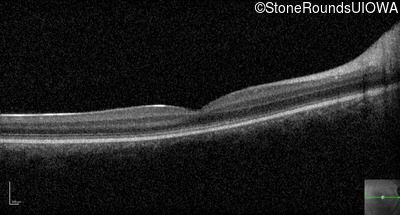

Optical Coherence Tomography - Right - 10/200

Exemplar / OCT Stack

Optical Coherence Tomography - Left - 10/100